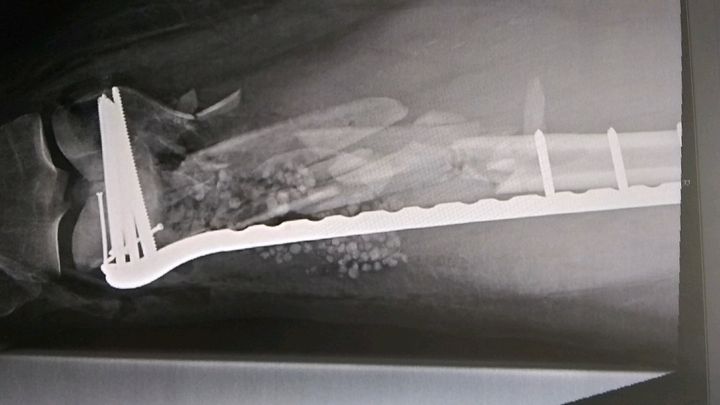

11/2 Update! So Al had his post op 2 week visit, surgeon said he has bone splinters and you can totally see the mess that is his leg in his x rays so Al is not arguing, but he is unhappy about being stuck in a rehab facility in Sacramento still. He will be there for awhile longer in case any of those splinters start moving or anything else goes wrong. It’s pretty technical stuff and our hospitals can’t handle it. So your donations are critical and thank you! He can’t do much from the hospital bed or wheelchair in Sacramento. Looks like a few more weeks to a month before he can possibly return home. They say there’s a 70% chance he won’t need a bone graft surgery so fingers crossed.

He was life flighted to Sacramento UCDavis and they managed to save his leg, but it’s going to be months of wheelchairs and a very hard road, unable to work or even drive. He’s got a broken right ankle and left femur that’s being plated together (it was poking out of his leg), hopefully won’t need a bone graft… and many other more minor injuries. You all know Al has a heart of gold and he’d do it for you. Donate if you can. Help him pay his bills for a couple months at least so he can get back on two wheels! Thank you.